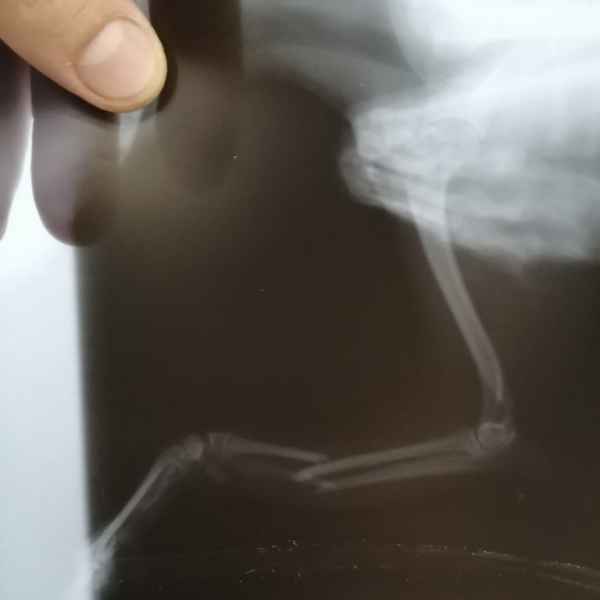

Вот что значит неудачно спрыгнуть с дивана. Это рентгеновские снимки одного из наших пациентов. Сначала хозяева обратили внимание на хромоту, а потом поняли, что у питомца очень болит лапа. Ещё бы не болело - поперечный перелом костей предплечья. Операция, установка DCP-пластины, восстановление, и он снова активный и жизнерадостный.

Этот пациент поступил к нам с кусаной раной левой грудной конечности После рентгенологического исследования обнаружили перелом костей предплечья. Сложность операции заключалось в том, что дистальный отросток лучевой кости был очень коротким. Хирургом нашей клиники было принято решение установить блокируемую lcp пластину. В данный момент пациент полностью восстановился..

Этот пациент поступил к нам после падения с 14 этажа. На основании комплекса исследований ,была установлена полиорганная недостаточность, перелом головки бедренной кости и трех пястных костей. Прием причинял сильную боль ,ведь был перелом нижней челюсти. Нами было принято решение по установке эгофагостомы. Ежедневно проводилась инфузионная терапия и только после полной стабилизации животного была проведена хирургическая операция по восстановлению костей.